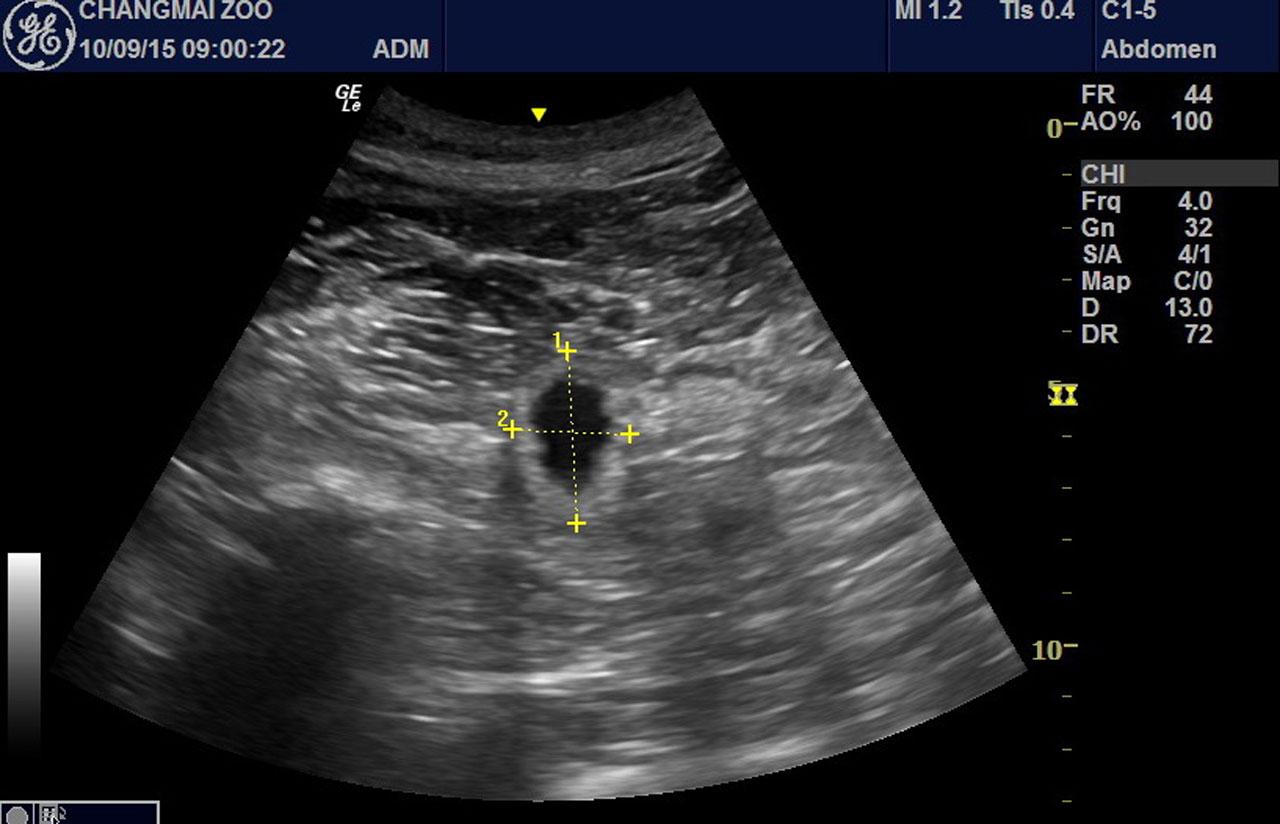

ทาง รศ.ดร.สุดสรร ได้เผยว่า จากการตรวจอัลตราซาวนด์ พบว่า ที่มดลูกหลินฮุ่ย หลังผสมเทียม ในวันที่ 81 มีโครงสร้างที่บ่งบอกว่า เป็นถุงหุ้มตัวอ่อนอย่างชัดเจน โดยมีขนาดกว้าง-ยาว ประมาณ 2.3 คูณ 2.7 ซม. แต่ยังตรวจไม่พบตัวอ่อนภายในถุงหุ้ม แต่พอมาถึง 82 วัน ก็คือ วันที่ 11 ก.ย.นี้ พบว่า ในตำแหน่งที่พบถุงหุ้มตัวอ่อนไปนั้น ได้พัฒนาไปเป็นลักษณะคล้ายโครงสร้างของตัวอ่อน ขนาดกว้างยาว 6.9 คูณ 1.9 ซม. แต่ยังไม่พบสัญญาณชีพใดๆ ซึ่งจากการตรวจ สามารถสรุปได้ 2 กรณี คือ กรณีพบถุงหุ้มตัวอ่อน ในวันที่ 81 นั้นเป็นการฝังตัวช่วงต้นในมดลูกหลินฮุ่ย โดยถุงหุ้มตัวอ่อนมีของเหลวอยู่ภายใน และไม่พบตัวอ่อน จากนั้น ตัวอ่อนจะเจริญอย่างรวดเร็ว ทำให้พบโครงร่างคล้ายตัวอ่อน ซึ่งในกรณีแรกนี้ ทำให้ค่อนข้างมั่นใจ ในการตั้งท้องของหลินฮุ่ย